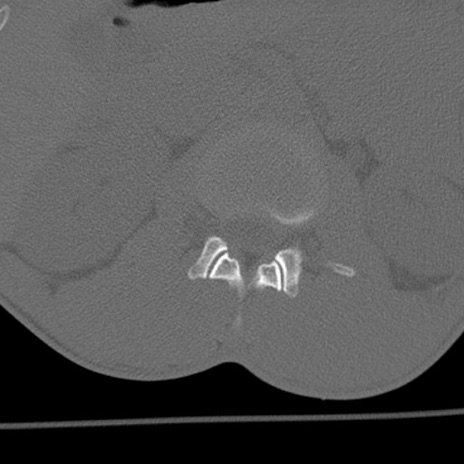

症例3 腰椎CT(横断像)

腰椎CT